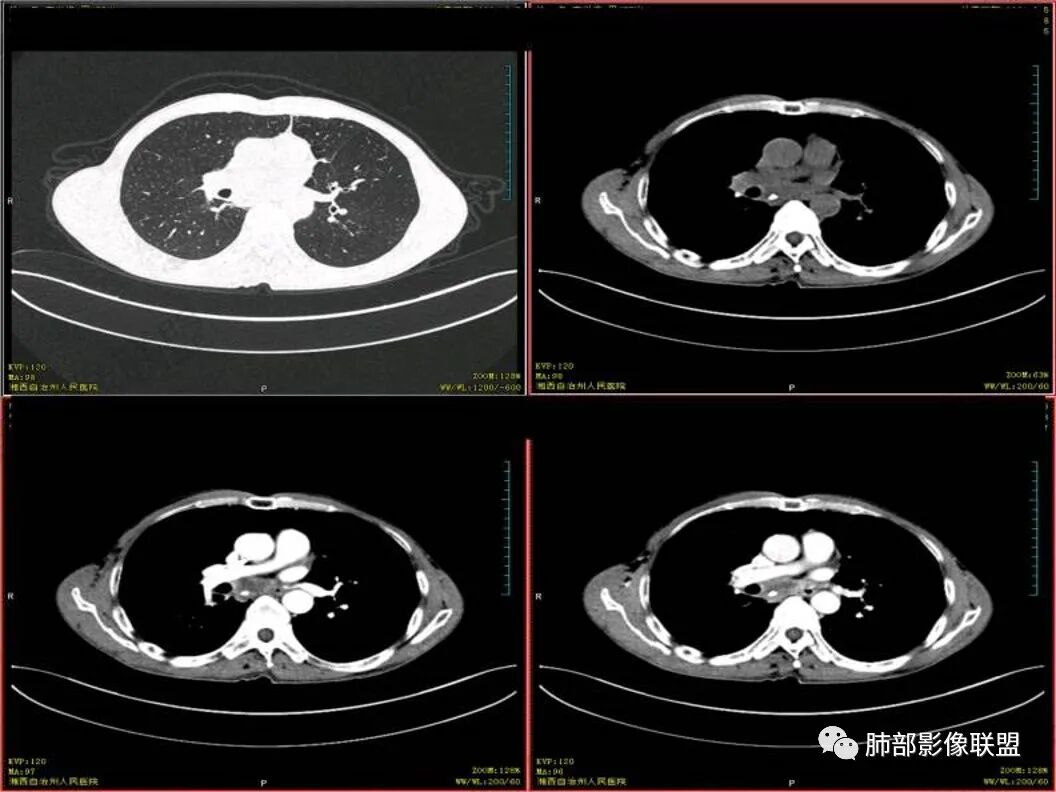

双上肺多发斑片、结节及条索影,边缘清晰,右肺下叶肿块,边缘分叶毛刺,密度不均有坏死,叶间胸膜及侧胸膜牵拉凹陷,斜裂可见六个核桃,周围小叶间隔呈串珠状,纵膈淋巴结肿大坏死,边缘可见钙化,考虑双肺结核,右下肺腺癌。鉴别鳞癌。

患者中年男性,以咳嗽 胸痛就诊

既往有肺结核病史

胸CT可见右肺下叶前基底段占位性病变,病灶周围可见周围不清毛玻璃影,病灶边缘可见分叶,呈膨胀性生长,纵隔窗可见病灶内呈偏心性坏死,增强扫描静脉期强于动脉期,纵隔隆突下淋巴结可见肿大坏死。

诊断考虑肺结核合并肺癌?

男性,咳嗽咳痰,无发热,以往结核并治疗中,两肺有结核背景,淋巴结增大钙化,右肺下叶病灶边缘模糊,内部坏死,坏死区边缘光整,实性部分强化均匀,血管通过截断

诊断:双肺tb+右肺下叶肺癌(鳞癌>腺癌)

双肺肺气肿伴纤维索条,结节影,以双上肺为主,部分可见支气管扩张,右肺下叶实性肿块,边缘毛糙,病灶较密实,支气管堵塞可能?平扫密度尚可,增强后不均匀强化,叶裂可见多个结节影,纵隔淋巴结肿大,考虑:肺癌伴陈旧性肺结核,肺脓肿伴陈旧性结核

双肺上叶多态,多灶,支持结核。右肺下叶肿块,边缘模糊,毛刺,胸膜牵拉,中央坏死,不均匀强化,似乎有壁结节,斜裂增厚,纵隔淋巴结肿大,二元,结核+鳞。鉴别结核+曲霉。

双上肺多发病灶,考虑结核(陈旧灶为主),右肺下叶前基底段占位,分叶、毛刺、胸膜牵拉,中央坏死,局部壁不光滑,前基底段支气管未见显示,不均匀强化,病灶远端阻塞性炎症,纵隔淋巴结肿大、融合。综合考虑恶性病变,鳞癌可能大。

双上肺多发条索及斑片状,局部支气管扩张,考虑结核。右下肺病灶分叶毛刺,胸膜牵拉,不均匀强化,坏死。纵隔淋巴结肿大,坏死,考虑右下肺肺癌并淋巴结转移,鳞癌可能。

中年男性,双肺多形性病变,双上肺纤维条索影及片状影,右肺下叶团块,有分叶,胸膜牵拉,毛刺,增强示坏死明显,坏死边界较清,也可能是容积效应,周围卫星灶,目测没看到明显支气管堵塞,一元考虑结核,二元考虑结核合并恶性肿瘤(鳞癌?)

临床 中年男性,咳嗽盗汗、老结核史,血沉高、t试验阳性,结核应该存在,cyf高4倍,价值怎么样待验证。影像 :两上肺实变加粗大索条灶,两肺野弥漫粟粒,考虑结核应该问题不大。重点分析右下病灶:隆突下淋巴结肿大,但伴钙化,有边缘强化?淋巴结融合又是恶性征像?右下肺病灶冠状位总体方正,横断位总体三角型,长毛刺、近端也有渗出、坏死彻底、空洞壁光滑锐利,似有边缘强化?看做薄壁空洞?以上符合炎性病灶。   支持恶性的征像 :冠状位的空洞似有壁结节,偏心坏死。   综合 ,右下肺鳞癌(偏心空洞+cfy)+两肺结核。

中年男,既往结核,慢性病程,有炎症指标增高和中毒症状。ct双肺上叶索条牵拉支扩伴有树丫,考虑陈旧性结核。

右下叶前基地段肿块,不规则边缘,周围树丫和长短毛刺,内部小空泡,强化后环形强化,纵膈淋巴结肿大,并有不规则环形强化和钙化,总体考虑感染性病变,结核病。

右下叶肿块鳞癌待除外。